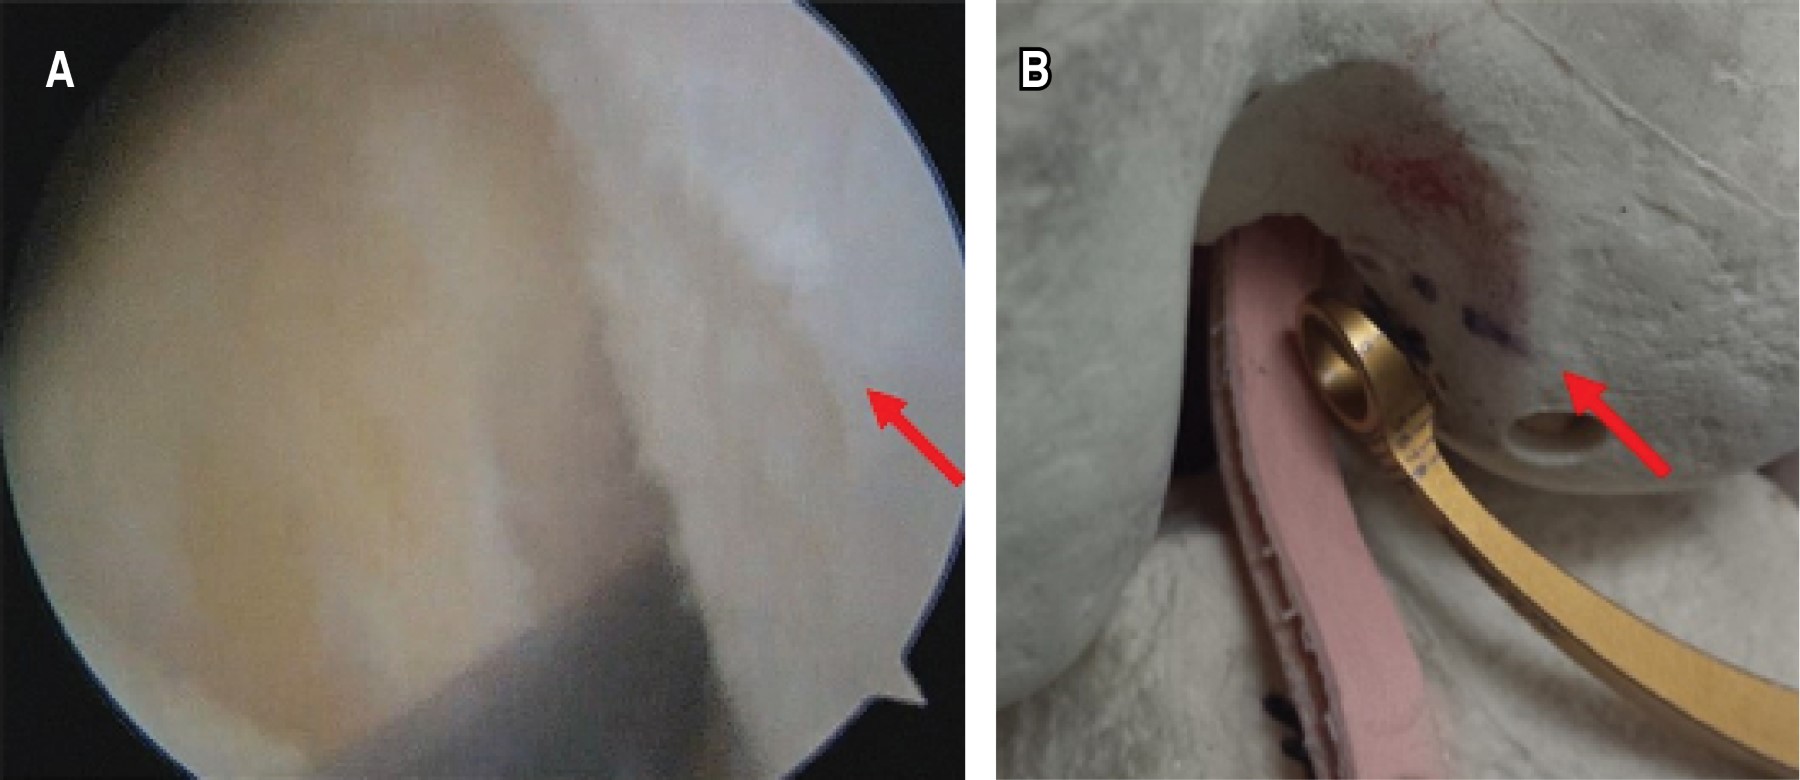

Experience in anterior cruciate ligament reconstruction using hamstring autograft with preserved insertion and anatomical femoral tunnel outside-in drilling

Despite of the controversies with the different techniques for anterior cruciate ligament reconstruction, a good option is a surgery using hamstring autograft with tibial preserved insertion, anatomical femoral tunnel outside-inside drilling and femoral fixation with an extra-articular interference screw. Because a graft without disinsertion preserves its biological properties, improving proprioception. In addition, the outside-in drilling technique allows to make an horizontal tunnel, achieving a greater graft bending angle that improves anteroposterior-rotational stability and reduces stress on the plasty. Finally, we prefer to use interference screws, considering that it is a reliable system that survive the passage of time and is the only system that allows to keep graft insertion. We share our experience with 32 procedures.

Figure 1

Figure 2

Figure 3

Figure 4